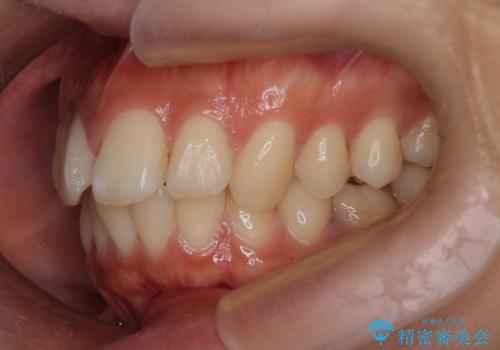

口元の突出感を解消し、横顔を美しく整えるワイヤー矯正

- 口元が出ていること(突出感)を気にされ、これを下げたいという主訴でご来院されました。精密な検査の結果、前歯を大きく後退させ、口元を改善するためには、スペースの確保が不可欠と診断しました。そこで、上下左右の第一小臼歯(4番目の歯)を計4本抜歯し、そのスペースを利用して前歯全体を奥へ移動させる抜歯矯正の治療計画を立案。確実な歯の移動を実現するため、ワイヤー矯正装置を使用しました。

今回の矯正治療では、口元の突出感を解消するためのスペースを確保するため、計画通り上下左右4本の小臼歯を抜歯しました。装置には、確実な歯の移動と細やかな調整が可能なワイヤー矯正を採用。抜歯によってできたスペースを最大限に利用し、前歯を奥へ、そして垂直的に慎重に移動させました。

治療の結果、長年のコンプレックスであった口元の突出感が大幅に解消され、横顔のライン(Eライン)が美しく改善しました。機能的な咬み合わせを確立すると同時に、患者様が望んでいた審美的な口元を獲得していただけました。